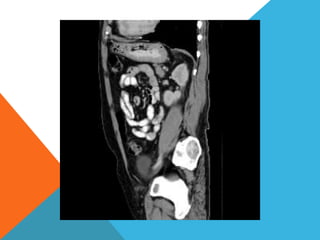

El paciente presentó síntomas de sangrado digestivo y pérdida de peso. Exámenes revelaron gastritis crónica asociada a H. pylori. Un tumor fue descubierto en una colonoscopia normal. La cirugía removió un tumor fibroide solitario, una rara neoplasia mesenquimal que usualmente crece lento y tiene bajo potencial de malignidad. El pronóstico después de la remoción quirúrgica es generalmente bueno.